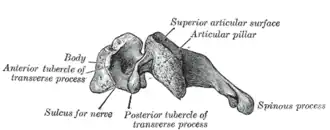

Le corps vertébral des vertèbres cervicales C3-C6 sont cubiques allongés transversalement.

Leur face supérieure est concave transversalement avec deux saillies latérales verticales : les uncus (ou apophyse semi-lunaire ou crochet ou apophyse unciforme)

Leur face inférieure est concave d'avant en arrière et convexe transversalement. Latéralement deux échancrures reçoivent les uncus de la vertèbre sous-jacente.

Les deux faces latérales reçoivent les racines antérieures des processus transverses. Leur bord antérieur se prolonge en bas formant un bec recouvrant la vertèbre sous-jacente. Leur bord postérieur se prolonge par les pédicules vertébraux. A l'arrière du pédicule s'attache la racine postérieure du processus transverse.

Les foramens (ou trous) transversaires sont formés par la face externe des pédicules, les deux racines du processus transverse et leur jonction. C'est le passage des artères vertébrales et des veines vertébrales.

La face supérieure de la jonction osseuse du processus transverse est creusé du sillon du nerf spinal pour le passage de ces derniers. Le sommet du processus porte deux tubercules : les tubercules antérieur et postérieur du processus transverse.

Les bords supérieur et inférieur des pédicules sont échancrés pour former avec les vertèbres voisines les foramens intervertébraux.

À l'arrière des pédicules les lames vertébrales se dirigent en bas, en arrière et en dedans. Elles sont plus longues que hautes. Elles portent en arrière le processus épineux court et large portant une gouttière inférieure recevant le bord supérieur du processus épineux sous-jacent. Son sommet porte deux tubercules.

À l'union des lames et des pédicules une colonne osseuse porte les processus articulaires supérieurs et inférieurs. La surface articulaire supérieure est orientée en arrière, en haut et légèrement en dehors. La surface articulaire inférieure est orientée en avant, en bas et légèrement en dedans.

Le tubercule antérieur du processus transverse de la sixième vertèbre cervicale, plus proéminent que les autres, est un repère chirurgical important car il est au niveau du croisement des artères carotide commune, thyroïdienne inférieure et vertébrale. Il est nommé tubercule carotidien ou tubercule de Chassaignac[1].